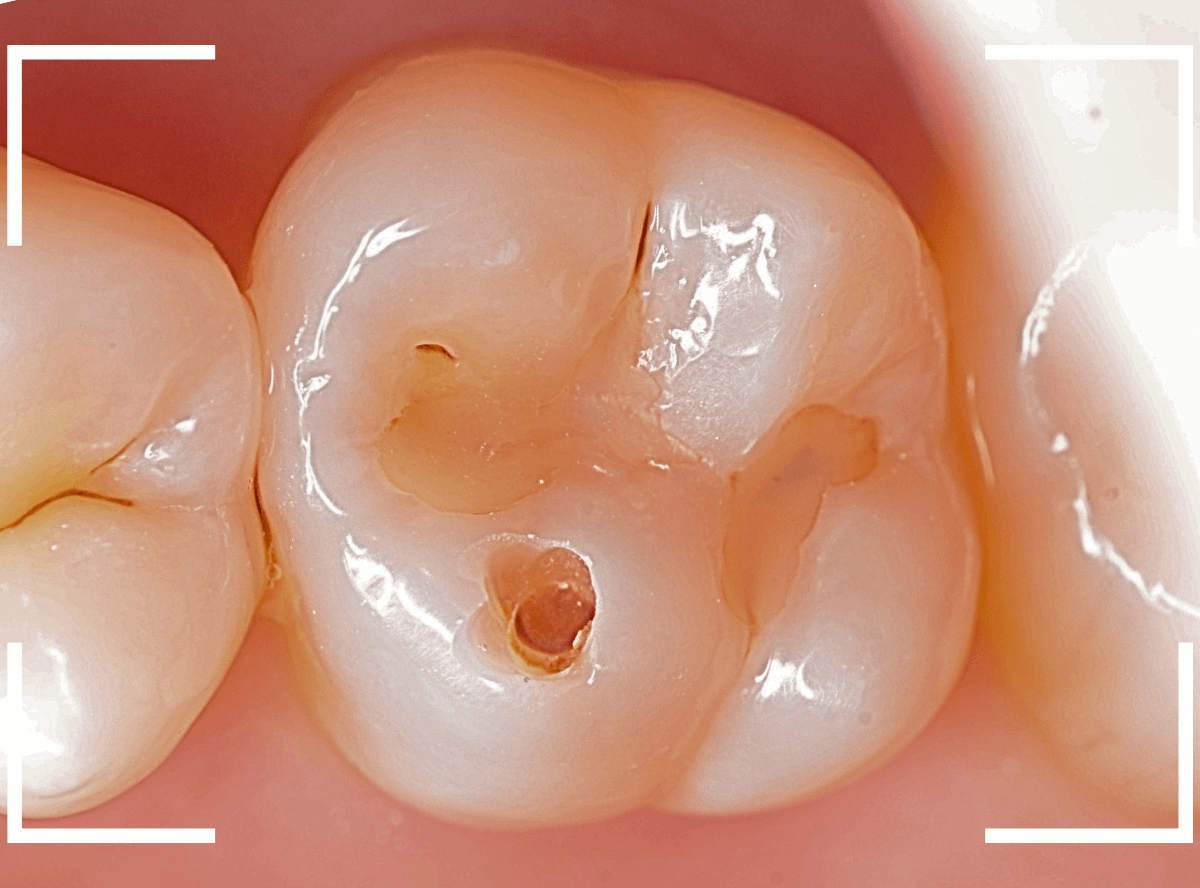

Case.7 レントゲンに写らないレジンの中の虫歯を削って調べる

こちらも定期検診希望で来院された患者さんです。

特に症状はありませんが、歯の咬頭(噛み合わせの山の部分)に小さな穴が空いていて、その周りがもやっと黒く見え、虫歯が怪しいです。

レントゲン写真で確認しますが、ここでは特に問題はなさそうに見えます。

患者さんに状況を説明し、慎重に削って調べる事になりました。

少しずつ穴の部分を削ってみると、ズブッと落とし穴にはまるような柔らかい虫歯の層(=軟化象牙質)に当たりました。

慎重に虫歯を除去したところです。

歯の溝のレジンが詰めてあった部分まで虫歯は進行していました。

とはいえ、それほど深く虫歯は進行していませんでしたので、虫歯除去後、レジンを充填して治療は終われました。

このように定期的にメンテナンスに来ていただくと虫歯が本格的に進行する前に対処する事ができます。